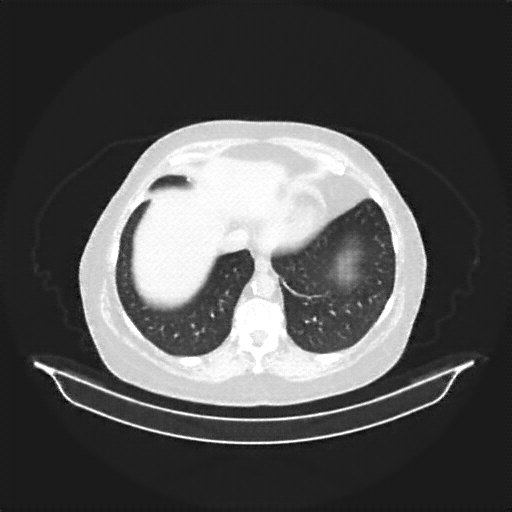

Original NATIVE CT scan (input)

Full window (WL 1023.5, WW 4095 β†’ Low βˆ’1024, High +3071)

Lung window (WL -600, WW 1500 β†’ Low βˆ’1350, High +150)

Mediastinum window (WL 40, WW 400 β†’ Low βˆ’160, High +240)